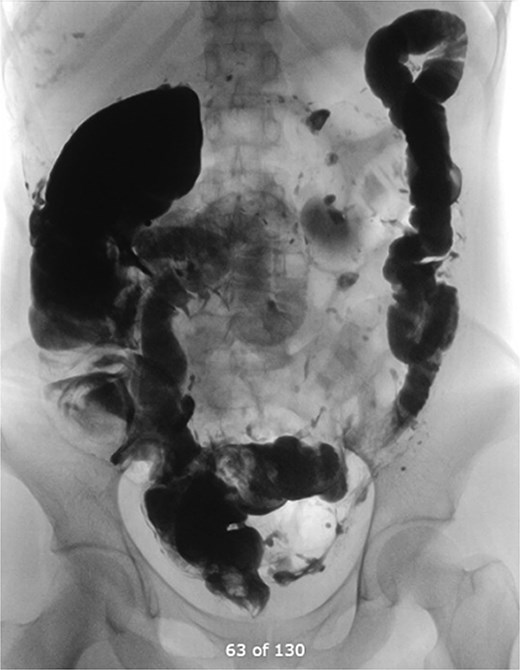

Contrast-enhanced CT of the abdomen and pelvis revealed extensive barium extravasation outlining the peritoneal cavity, accompanied by pneumoperitoneum (Fig. 3). Two barium-outlined, walled-off intra-abdominal collections were identified: one located anterior to the lower pole of the left kidney and the other in the pelvis, anterior to the rectum (Figs 4 and 5). Due to significant barium-related imaging artifacts, the precise site of bowel perforation was not identified. A diagnosis of peritonitis secondary to barium spillage was established, with associated intra-abdominal collections.

CT contrast abdomen and pelvis showing spill of barium outlining the peritoneal cavity. Stoma at the right side of the abdomen (A).